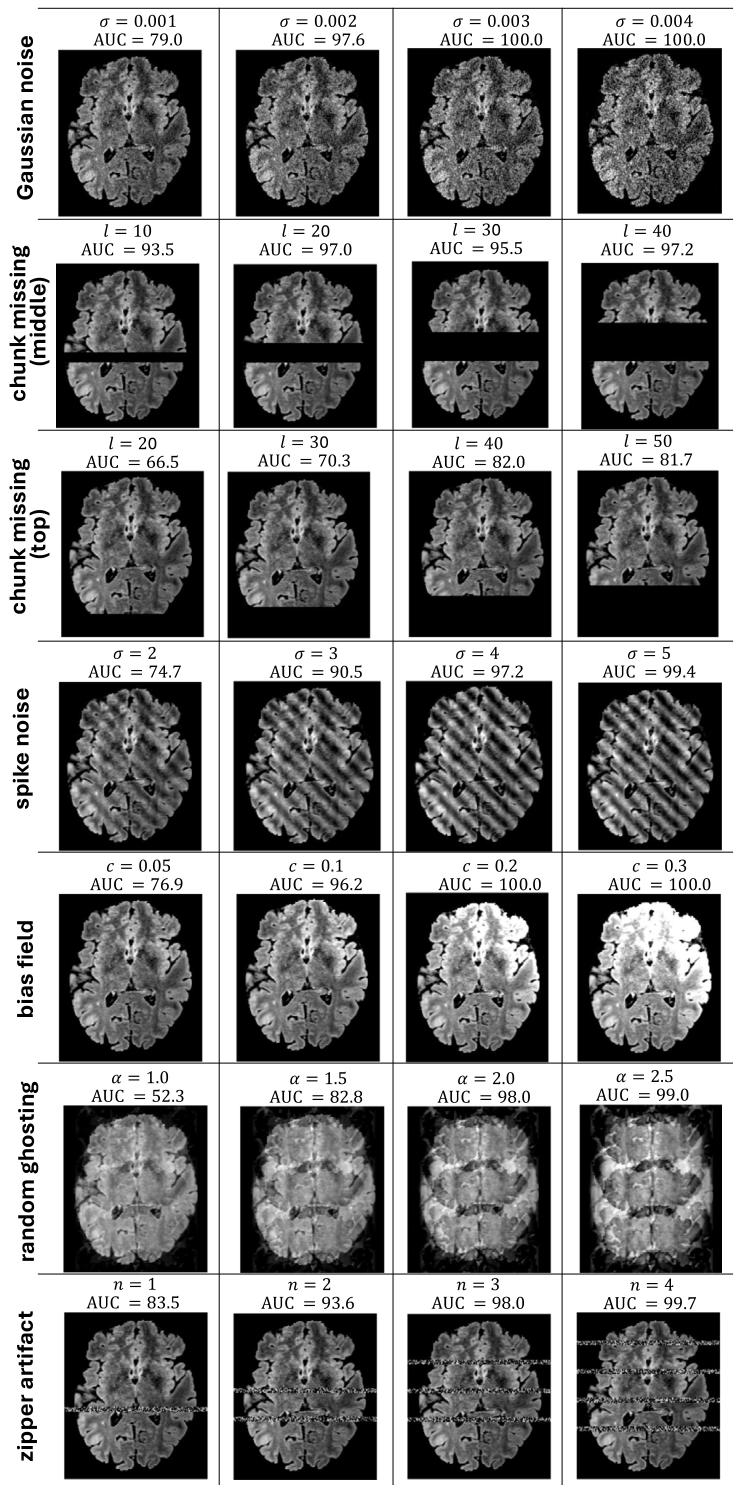

Fig. 6. Visualization of different extents of synthetic anomaly added to the image, along with 𝐴𝑈𝐶 score of the model’s anomaly detection performance.

图6 图像中添加不同程度合成异常的可视化结果,以及模型异常检测性能的AUC值